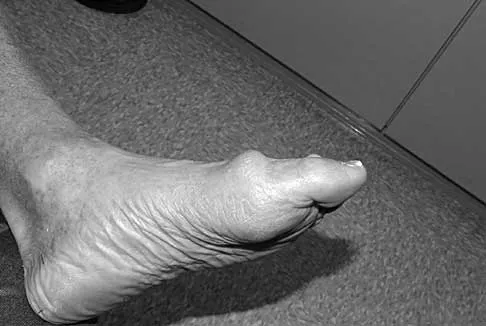

A 6-year-old girl has the bilateral foot deformity shown in Figure 1. There is no family history of disease. Examination reveals fixed hindfoot equinus, and muscle function testing shows strong posterior tibial function, fair plus anterior tibial function, poor peroneal function, and strong gastrocnemius function. A Coleman block test shows a correctable hindfoot. Nerve conduction velocity studies show diminished function in the peroneal and ulnar nerves on both sides. Pathologic changes found in a sural nerve biopsy include "onion bulb" formation, and DNA testing confirms the presence of a mutation in the MPZ gene, consistent with hereditary motor sensory neuropathy type III (HMSN-III). What is the best course of action?

Explanation

The patient has HMSN-III or Dejerine-Sottas syndrome. This form of HMSN progresses very rapidly and frequently results in severe foot deformity in early childhood. The changes are progressive and are the result of muscle imbalance during growth. Balancing of the foot musculature is essential, particularly during the phases of rapid growth of the foot. However, this cannot be accomplished using the anterior tibial muscle because it is already weak and the transfer will further weaken it. Bony procedures also may be required, and tendon transfers cannot be depended on to correct bony deformity. However, these procedures can be deferred until the foot is closer to adult size. Surgeries that lead to joint arthrodesis, such as triple arthrodesis and some midfoot osteotomies, are contraindicated because the feet may lose protective sensation as the disease progresses. Fusions in insensate feet are less successful than realignment procedures that maintain mobility. Wetmore RS, Drennan JC: Long-term results of triple arthrodesis in Charcot-Marie-Tooth disease. J Bone Joint Surg Am 1989;71:417-422. Roper BA, Tibrewal SB: Soft tissue surgery in Charcot-Marie-Tooth. J Bone Joint Surg Br 1989;71:17-20.